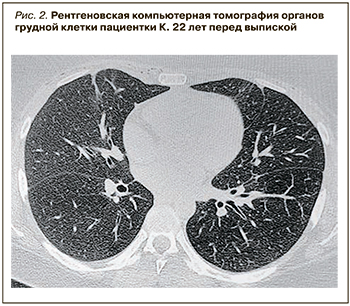

ОАК в динамике без признаков воспалительной реакции: лейкоциты – 7,4×109/л; лейкоформула: п/я – 4%, с/я – 50%, э – 3%, м – 6%, лимф – 37%, СОЭ – 5 мм/ч по Панченкову. СРБ 4,3 мг/л, прокальцитонин 0,037 нг/мл. На повторной РКТ ОГК через 9 дней от начала терапии положительная динамика в виде частичного разрешения альвеолярного уплотнения легочной паренхимы, уменьшения проявлений эмфиземы мягких тканей и пневмоперикарда (рис. 2).

ОАК в динамике без признаков воспалительной реакции: лейкоциты – 7,4×109/л; лейкоформула: п/я – 4%, с/я – 50%, э – 3%, м – 6%, лимф – 37%, СОЭ – 5 мм/ч по Панченкову. СРБ 4,3 мг/л, прокальцитонин 0,037 нг/мл. На повторной РКТ ОГК через 9 дней от начала терапии положительная динамика в виде частичного разрешения альвеолярного уплотнения легочной паренхимы, уменьшения проявлений эмфиземы мягких тканей и пневмоперикарда (рис. 2).